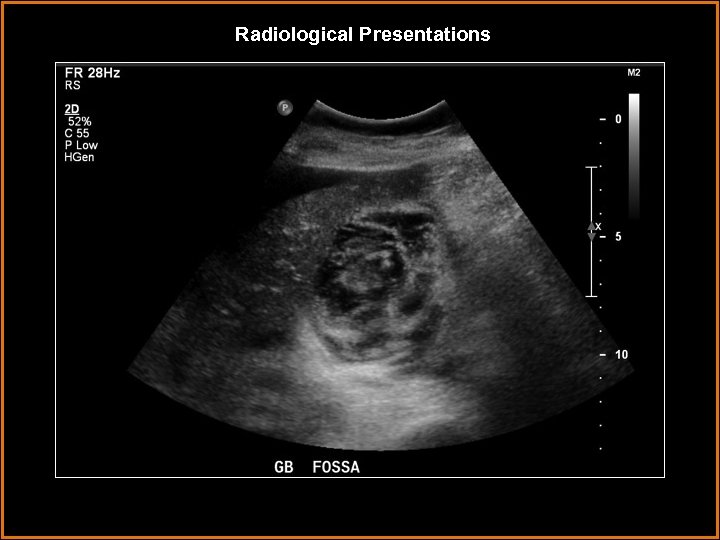

Findings and Differentials Findings: Striated thickening of the gallbladder wall with multiple hyperechoic, serpentine Findings and Differentials Findings: Striated thickening of the gallbladder wall with multiple hyperechoic, serpentine bands separated by hypoechoic areas. Also, intraluminal membranes concerning for desquamative mucosa. Differentials: • Acute cholecystitis – Wall thickening and pericholecystic fluid are neither sensitive nor specific. The most sensitive finding is a gallbladder stone with a positive Murphy’s sign. • Hydatid cyst – intrahepatic cystic lesion with floating membranes or multiseptated cysts. • Emphysematous cholecystitis – dirty shadowing from gas in gallbladder wall. • Volume overload – usually uniform, homogeneous wall thickening.

Discussion • Gangrenous cholecystitis is on the severe end of the spectrum of acute Discussion • Gangrenous cholecystitis is on the severe end of the spectrum of acute cholecystitis. • It is thought to be a result of tension in the gallbladder wall secondary to increased distention. This results in ischemic necrosis of the gallbladder wall, sometimes due to cystic artery thrombosis. • The condition occurs in older patients, usually male. Coexisting vascular disease is commonly seen. Sonographic Murphy’s sign is usually absent, thought to be due to devascularization and denervation. • On ultrasound, the primary finding is layered or striated gallbladder wall thickening. Usually, it is irregular with luminal projections. Less often seen, but more specific, are intraluminal membranes that are thought to represent desquamative mucosa.